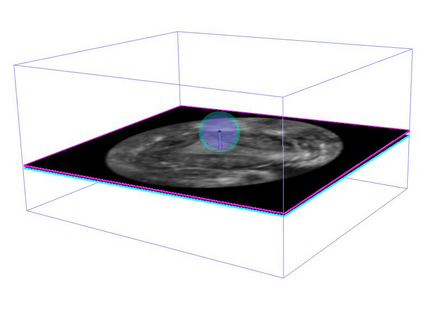

Standard plane (SP) localization is essential in routine clinical ultrasound (US) diagnosis. Compared to 2D US, 3D US can acquire multiple view planes in one scan and provide complete anatomy with the addition of coronal plane. However, manually navigating SPs in 3D US is laborious and biased due to the orientation variability and huge search space. In this study, we introduce a novel reinforcement learning (RL) framework for automatic SP localization in 3D US. Our contribution is three-fold. First, we formulate SP localization in 3D US as a tangent-point-based problem in RL to restructure the action space and significantly reduce the search space. Second, we design an auxiliary task learning strategy to enhance the model's ability to recognize subtle differences crossing Non-SPs and SPs in plane search. Finally, we propose a spatial-anatomical reward to effectively guide learning trajectories by exploiting spatial and anatomical information simultaneously. We explore the efficacy of our approach on localizing four SPs on uterus and fetal brain datasets. The experiments indicate that our approach achieves a high localization accuracy as well as robust performance.